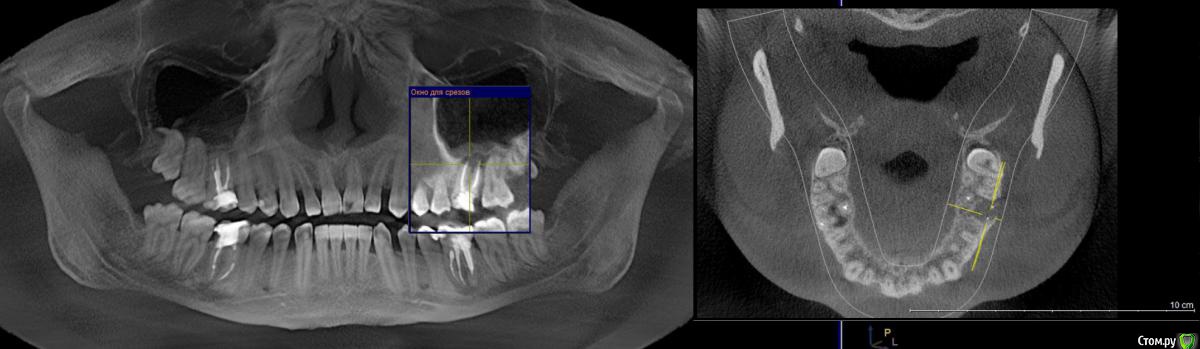

WHITE_ANTONIO Опубликовано 7 декабря, 2015 Автор Поделиться Опубликовано 7 декабря, 2015 Добрый вечер, прикладываю скриншоты КТ Ссылка на комментарий

DmitrySH Опубликовано 7 декабря, 2015 Поделиться Опубликовано 7 декабря, 2015 Прицельный снимки еще будут нужны, в хорошем качестве.26 - ничего особого не видно, просто периодонтит36 - перерасширены каналы, возможно наличие трещины или перфорации.16,46 - тоже требуют лечения Ссылка на комментарий

DmitrySH Опубликовано 7 декабря, 2015 Поделиться Опубликовано 7 декабря, 2015 (изменено) на основании данного снимка судьба зуба 36 под вопросом,а 26 - непонятно, но пока не увидел ничего ужасного. Изменено 7 декабря, 2015 пользователем DmitrySH Ссылка на комментарий

DmitrySH Опубликовано 7 декабря, 2015 Поделиться Опубликовано 7 декабря, 2015 Но я не смотрю на очаги воспаления, меня интересует целостность твердых тканей зуба. Исходя из этого и строится прогноз. На КТ любой материал "фонит" и выглядит больше чем есть. Соответственно есть непонятные моменты. 1 Ссылка на комментарий